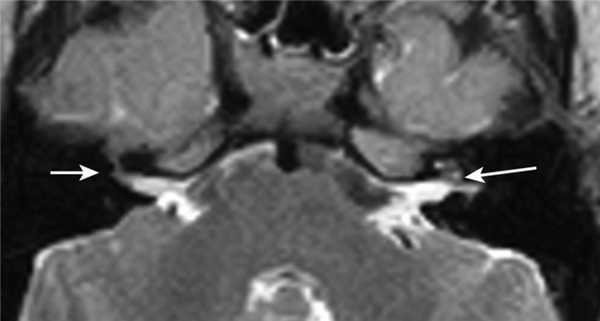

Пациентке была выполнена МРТ основания черепа по описанной методике (рис. 1). Рисунок 1. МРТ основания черепа больной Ф. с хроническим правосторонним гнойным средним отитом. Фистула лабиринта. Холестеатома. а — исследование в режиме Т1; б — в режиме Т2; в — в режиме non-EPI DWI.

В режиме Т1 справа определяется образование с низкой интенсивностью сигнала, а в режиме Т2 и non-EPI DWI — образование с гиперинтенсивным сигналом. Диагноз: хронический правосторонний гнойный средний отит; холестеатома; фистула лабиринта. Пациентка была подвергнута санирующей операции на правом ухе с тимпанопластикой и облитерацией паратимпанальных пространств. Были выявлены холестеатома, заполняющая аттик, адитус, антрум, деструкция цепи слуховых косточек, фистула латерального полукружного канала. Послеоперационный период протекал без особенностей, на 15-е сутки была удалена гемостатическая губка и силиконовая выстилка. При контрольном осмотре ухо сухое, отмечает улучшение слуха, головокружения нет. Через 12 мес проведено повторное МРТ-исследование. Признаков холестеатомы не обнаружено. Получен хороший функциональный результат — ухо толерантно к воде, самоочищается.